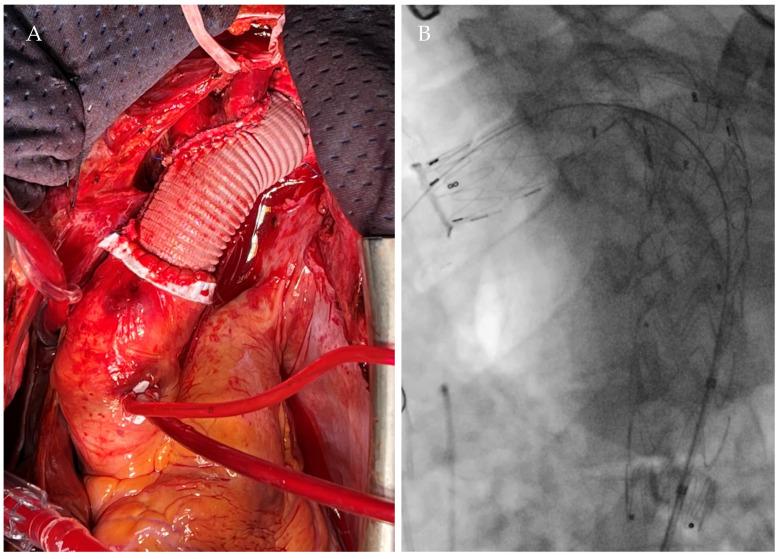

Grade I-II blunt traumatic aortic injuries (BTAIs) are typically managed conservatively, but their long-term progression is poorly understood. Chronic pseudoaneurysms may develop years after the injury, often remaining asymptomatic and being incidentally diagnosed. Two cases of post-traumatic aortic pseudoaneurysms, detected 20 and 25 years following conservatively managed BTAIs, are reported. Additionally, a comprehensive review of all post-traumatic pseudoaneurysms reported in the MedLine (PubMed.gov, U.S. National Library of Medicine, National Institute of Health) database between January 1984 and December 2024 was performed. Both our patients underwent successful hybrid procedures, with no complications at the 1- and 4-year follow-ups. Our literature review identified 37 patients across 22 studies, with 32.4% presenting asymptomatically or incidentally diagnosed through routine imaging, between 1 month and 50 years after the initial trauma. In 37.8% of cases, the patients underwent open or endovascular repair. This case series and literature review emphasize the importance of long-term follow-up for patients with conservatively managed BTAIs, as chronic complications such as aortic pseudoaneurysms can arise decades later. Continuous surveillance is critical to ensure early detection and management.

I-II级钝性创伤性主动脉损伤(BTAIs)通常采用保守治疗,但其长期进展情况尚不清楚。慢性假性动脉瘤可能在损伤数年之后形成,常常没有症状,而是在偶然检查时被诊断出来。本文报告了两例在保守治疗BTAIs后20年和25年发现的创伤后主动脉假性动脉瘤病例。此外,还对1984年1月至2024年12月期间MedLine(美国国立医学图书馆、美国国立卫生研究院的PubMed.gov)数据库中报告的所有创伤后假性动脉瘤进行了全面综述。我们的两名患者均成功接受了杂交手术,在1年和4年随访时均无并发症。我们的文献综述在22项研究中确定了37例患者,其中32.4%在初次创伤后1个月至50年之间没有症状或通过常规影像学检查偶然被诊断出来。在37.8%的病例中,患者接受了开放手术或血管腔内修复。这个病例系列和文献综述强调了对接受保守治疗的BTAIs患者进行长期随访的重要性,因为诸如主动脉假性动脉瘤等慢性并发症可能在数十年后出现。持续监测对于确保早期发现和治疗至关重要。